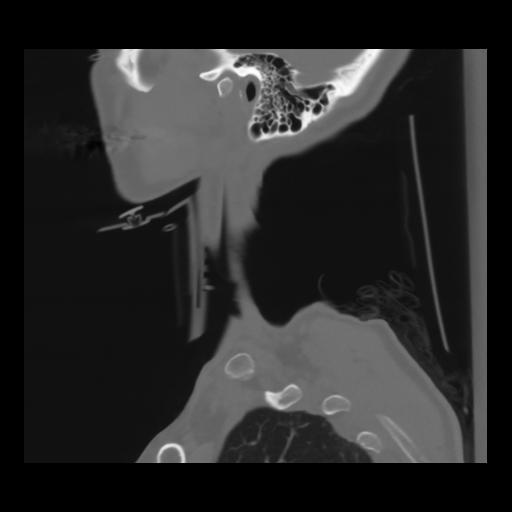

14 P.BLANDAS,,Sagittal,2.000,P.BLANDAS,Sagittal,